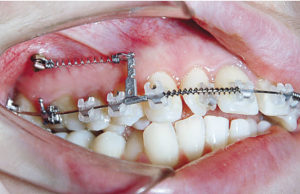

Применение ретрактора в ортодонтии

Ретрактор считается одним из важных помощников в современной ортодонтии.

Применение винтов в практике ортодонта

Современный ортодонтический винт — это малая система по выравниванию зуба в правильное положение, используют как дополнительные атрибут.